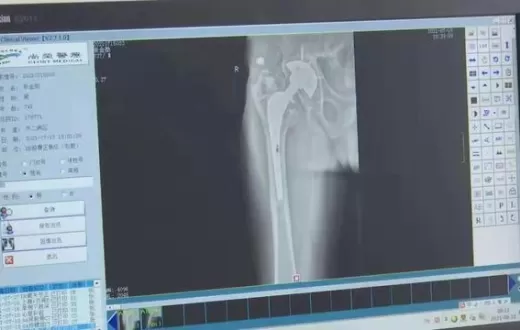

医院“量身定制”3D打印髋关节假体 让患者家门口重获新生

宁阳县第一人民医院:3D打印技术造福骨科患者